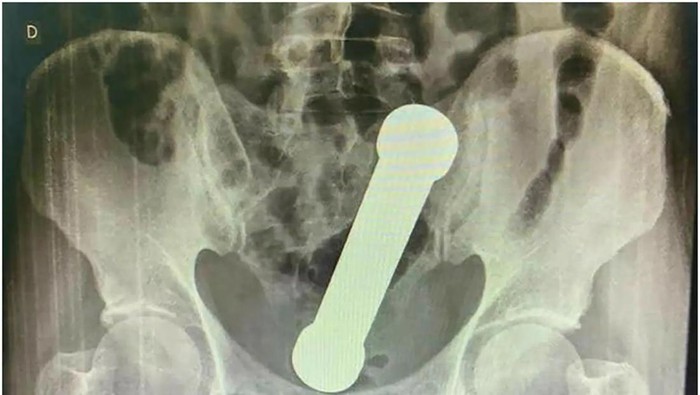

Setelah pemeriksaan anal awal gagal mengungkap apa pun, dokter memutuskan untuk memindai wilayah tersebut dengan x-ray. Mereka menemukan barbel sepanjang 20 cm bersarang di persimpangan usus besar dan dubur seperti mainan seks yang rumit.